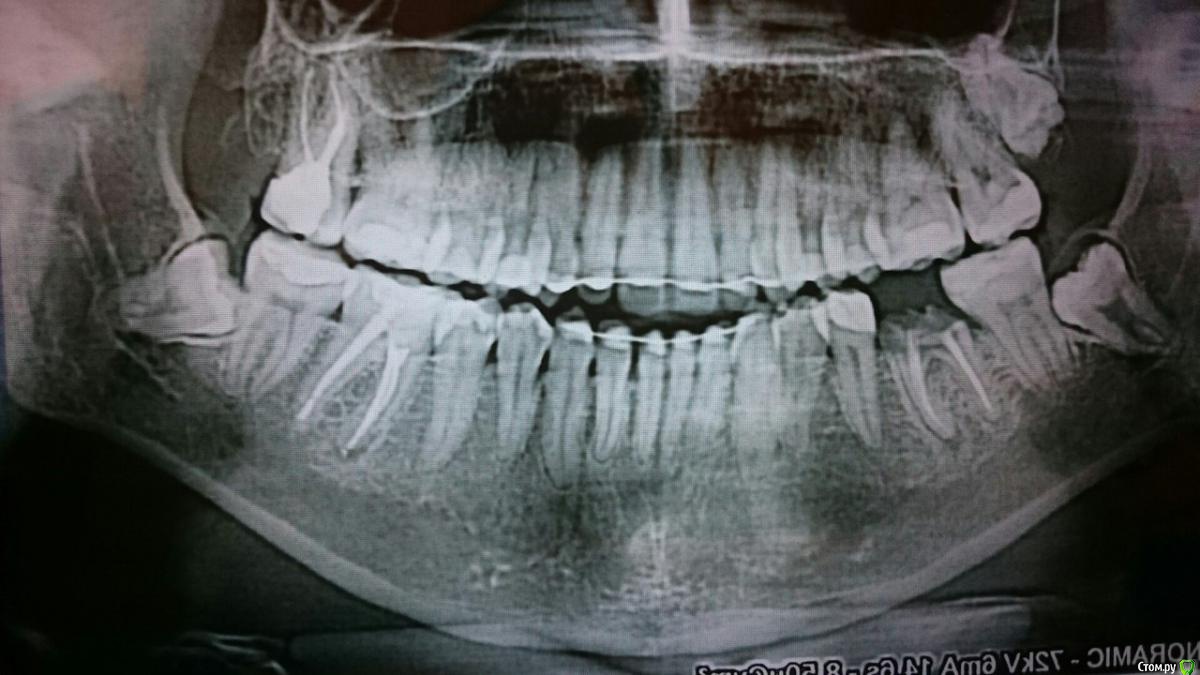

Libelle888 Опубликовано 22 февраля, 2019 Автор Поделиться Опубликовано 22 февраля, 2019 конечно, но нужен новый снимокВот снимок от июня 2018, но качество не очень 1 Ссылка на комментарий

red_butler Опубликовано 22 февраля, 2019 Поделиться Опубликовано 22 февраля, 2019 Не вижу препятствий для планового удаления, артикаин не проникает в молоко. Верхние третьи моляры редко приводят к серьезным проблемам, скорее всего, если он прорежется, то сразу начнёт травмировать щеку. Ссылка на комментарий